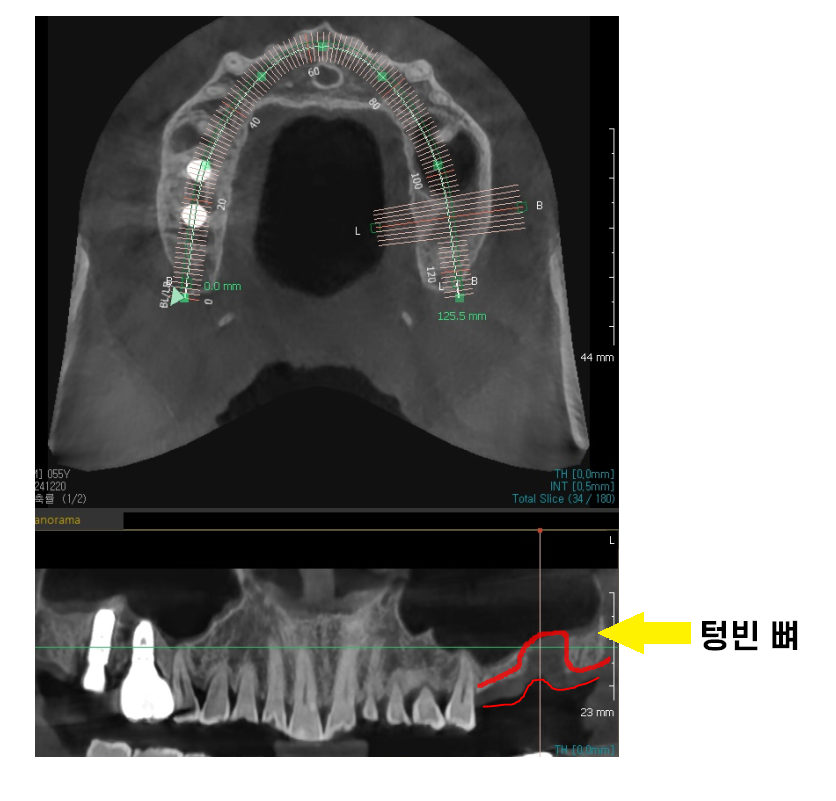

미사역 임플란트 치료에서 중요한 요소는

나이보다 뼈 상태입니다!

임플란트는 뼈에 식립하는 것이기 때문에

뼈만 튼튼하고

전신 상태가 건강하시면

나이가 많아도

복용하는 약물이 많다고 해서 수술이 불가능한 것은 아닙니다.

241220 나이가 젊어도 뼈가 없으면 임플란트 식립이 어렵습니다.

뼈 상태를 보아야한다!!

잇몸뼈만 충분하고 튼튼하면

임플란트는 잘 고정될 수 있답니다.

250317 뼈 상태에 따라 수술법이 달라집니다.